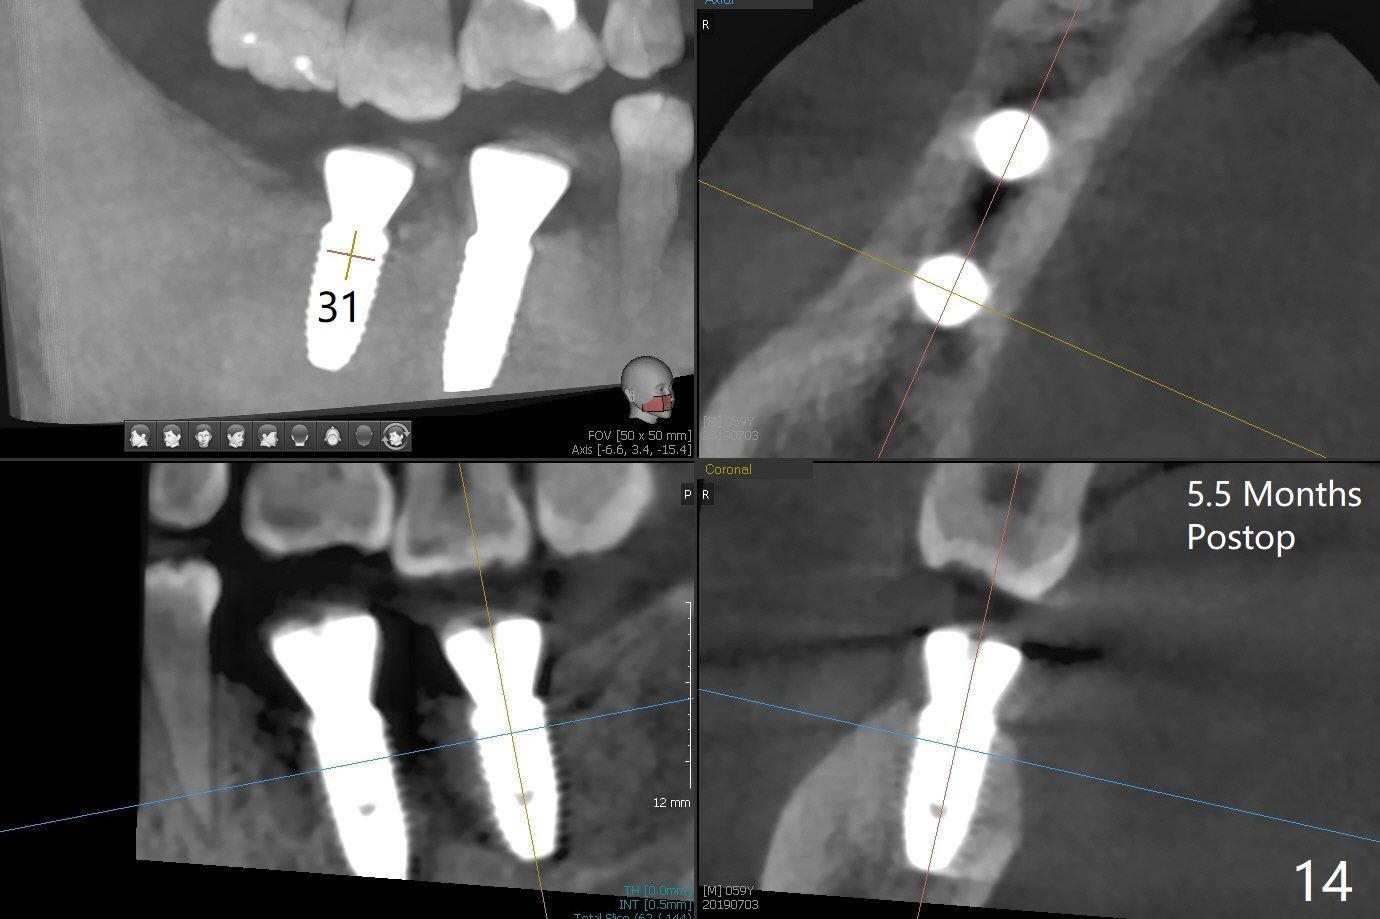

Abutment vs. Definitive One

After extraction of the tooth #30 with lingual subgingival fracture (Fig.1), the septum is fairly large (Fig.2 S). A bony vertical anchor pin (Fig.3 *) is inserted in the septum following pointed drill to to stabilize the guide during osteotomy and implant placement of #31. When the latter is finished, a fixture anchor pin is used at #31 as planned. A healing abutment is placed at #31 because of supraeruption of the tooth #2 (Fig.4,5), while a cementation abutment is placed at #30 (Fig.5) with autogenous bone (from drills) and allograft placed around it (*, Fig.6). Finally an immediate nonfunctional provisional is fabricated to keep the bone graft in place (Fig.7 P). The bone graft remains in place gel-like nearly 1 month postop (Fig.8). CBCT axial section shows that there is not enough space for mini implant placement at the tooth #2 (Fig.9). Restoration-induced intrusion will be conducted using the implants at #30 and 31 three-4 months postop. The buccal gingiva (Fig.10 *) is lingual to the provisional (P) nearly 1.5 months postop. When the provisional is removed, it appears that the mesiobuccal bone graft has lost (Fig.11). Two days later, the cementation abutment is loose and removed; the gingival cuff looks healthy (Fig.12). A 6.8x5 mm healing abutment is placed (Fig.13). In 2.5 to 3 months, abutments will be placed at #30 and 31. Splinted provisional will be fabricated over supraocclusion to intrude the tooth #2 with a stop on the left side. Surprisingly the patient agrees to intrude the tooth #2 with 2 mini implants 5.5 months postop (Fig.14,15). However, the miniimplants dislodged. Due to coronavirus, the implants are restored with heavy abutment and opposing tooth trimming 1 year 9 months postop (Fig.16). Magicore should have been placed instead.